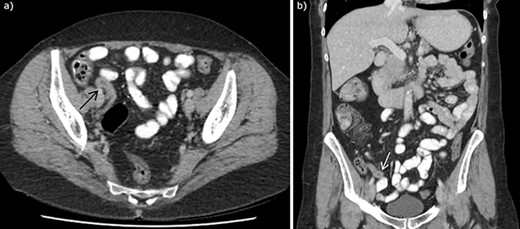

A 56 year old woman presented to emergency with seven days of abdominal pain. Her pain was initially dull and within the peri-umbilical region before migrating to the right iliac fossa and becoming sharp and constant. The pain was associated with subjective fevers and anorexia. There were no bowel or urinary symptoms reported. The patient was post-menopausal and before presentation was previously well with no significant past medical history; her only surgical history included two lower segment caesarean sections. She was seen by her general practitioner who arranged for an outpatient CT of the abdomen and pelvis with oral and intravenous contrast, undertaken on day six of symptoms. CT findings demonstrated a thickened appendix measuring up to 11 mm, reported as consistent with acute appendicitis. There was no significant fat stranding, intraperitoneal free fluid, nor gas, and the CT was otherwise unremarkable (Fig. 1). Upon presentation to emergency, examination found a clinically stable patient with tenderness in the right iliac fossa and suprapubic regions, particularly over McBurney’s point. Rosving’s sign was negative. White cell count was 6.8 × 109 cells/L, neutrophils 2.5 × 10^9 cells/L, C-reactive protein of 9.5 mg/L, while creatinine was slightly elevated at 96 μmol/L and electrolytes were within normal limits. She was incidentally found to be COVID-19 positive, however, was asymptomatic and was fully vaccinated. As her abdominal symptoms continued, she was taken to the operating theatre for a laparoscopic appendicectomy. This was completed unremarkably, with intra-operative macroscopic appearance of a thickened appendix without other abnormality, and the specimen routinely sent for histopathology. She was subsequently discharged from hospital without complication with resolution of her pain. Histopathology demonstrated mild acute mucosal appendicitis with occasional endometrial type glands with no stroma nor hemosiderin-laden macrophages, in keeping with endosalpingiosis (Fig. 2). There was no evidence of malignancy.

CT abdomen with intravenous and oral contrast demonstrating enlarged appendix, found to be appendiceal endosalpingiosis on histopathology of appendicectomy specimen, in (a) axial section and (b) coronal section. Arrows to enlarged appendix.